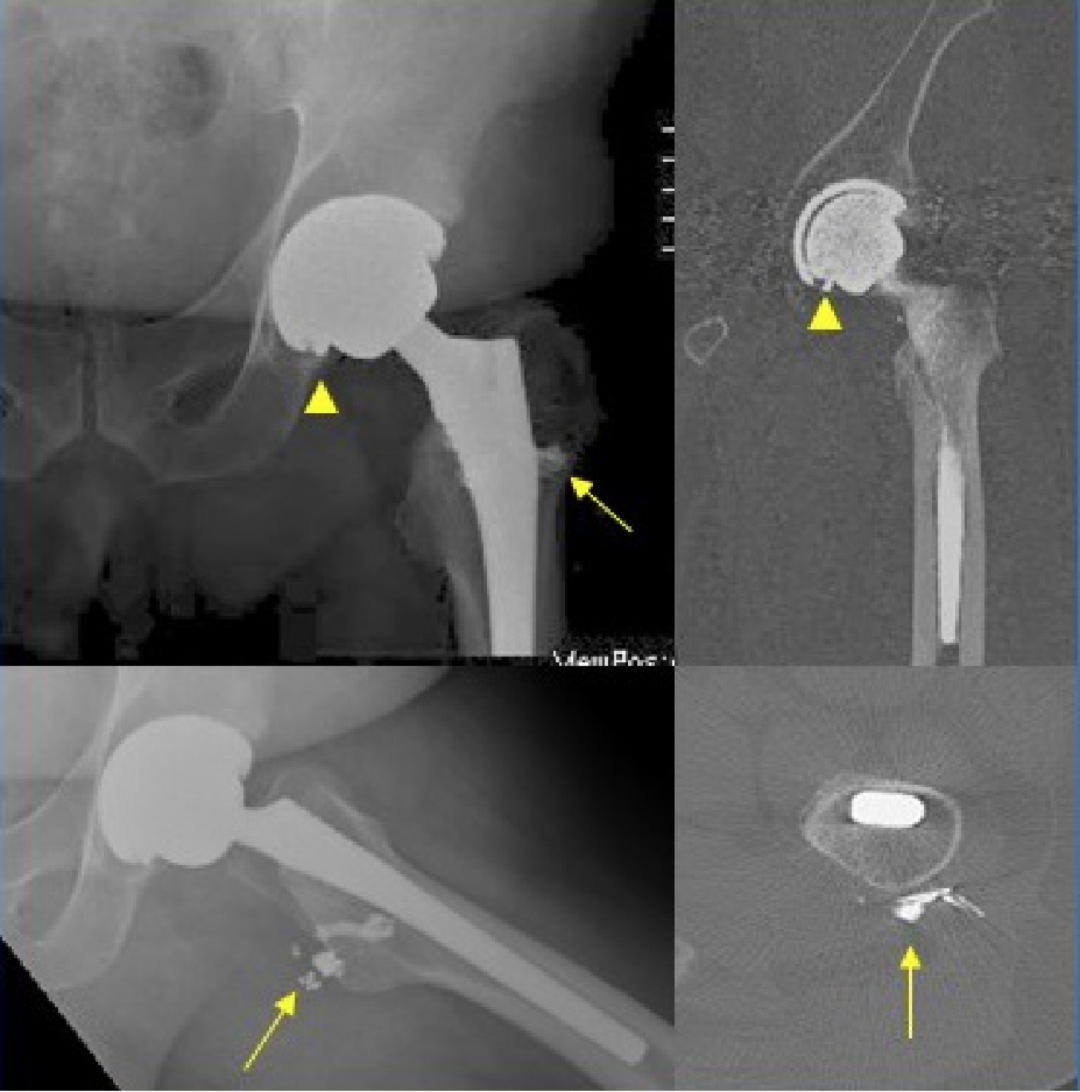

4.骨溶解:

发生率 5%~9%,与透亮线不同,地图样透亮区是由假体相关的骨水泥、金属或聚乙烯颗粒诱导的组织炎症反应所致(颗粒病)。

右侧髋臼及耻骨支骨质溶解吸收,关节周围团块状软组织肿块,围绕股骨头及股骨颈

7. 假体失败:

可发生于髋臼或股骨假体。

右侧全髋关节置换术后:聚乙烯磨损,股骨头在髋臼杯内位置不对称(箭头)